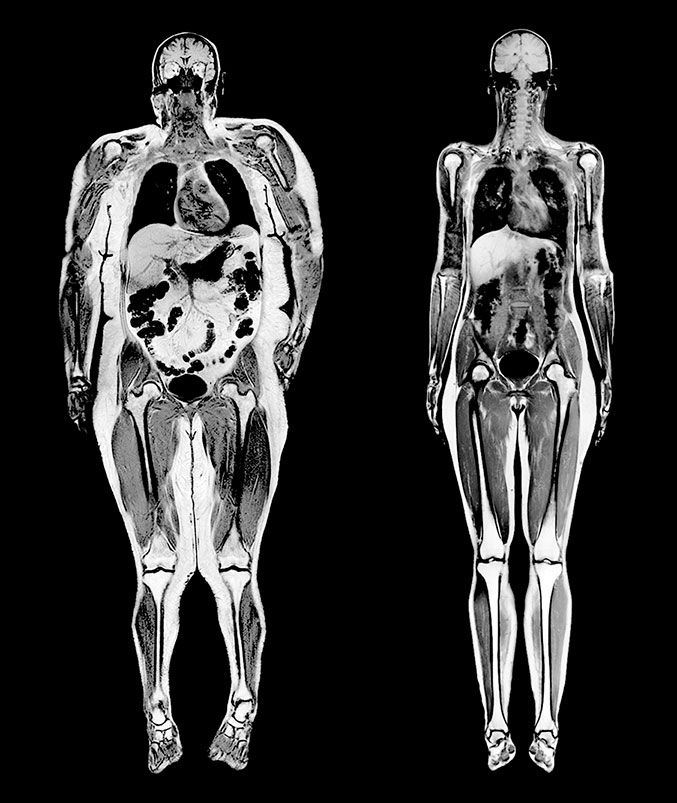

Думаете, жир скапливается только под кожей? Напрасно. На МРТ женщины весом в 114 кг, показанном в сравнении с МРТ женщины весом 54 кг, видны обширные отложения жира вокруг внутренних органов.

Изображение моего тела, полученное с помощью DEXA.